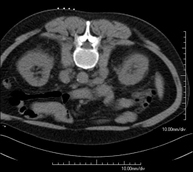

Prueba diagnóstica que consiste en obtener imágenes del abdomen de alta definición anatómica (hígado, vesícula biliar, vía biliar, páncreas, bazo, estómago, intestinos, riñones, estructuras vasculares, vejiga, útero y ovarios, etc.) mediante el empleo de un equipo de TC (Tomografía Computarizada). Dichas imágenes se estudian posteriormente en una estación de trabajo que permite reconstrucciones bidimensionales en diferentes planos del espacio, y también reconstrucciones 3D (volumétricas). La mayoría de estudios requieren el empleo de contraste yodado para mejorar la definición de las imágenes. - TC Pelvis

Prueba diagnóstica que consiste en obtener imágenes bi y tridimensionales del abdomen y de la pelvis de alta definición anatómica (estructuras óseas, estructuras vasculares, hígado, páncreas, vesícula biliar, riñones, glándulas suprarrenales, bazo, intestino delgado y grueso, vejiga, útero y ovarios, próstata y vesículas seminales, uréteres, etc.) mediante el empleo de un equipo de TC (Tomografía Computarizada). La mayoría de estudios requieren el empleo de contraste yodado. - TC Hígado